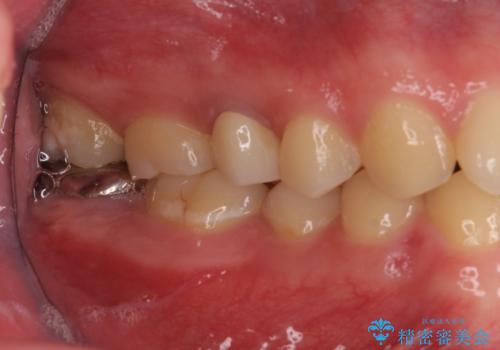

他院で虫歯治療を複数行っており、原因となりうる歯がいくつかありました。まずレントゲン上最もあやしい右上から治療開始しました。右上の歯は1本割れていたため、部分矯正で引っ張り出しました。

右上もう1本と左上は虫歯治療(セラミックインレー、セラミッククラウン)を行いました。

痛いところがなくなり、患者様には大変満足して頂きました。